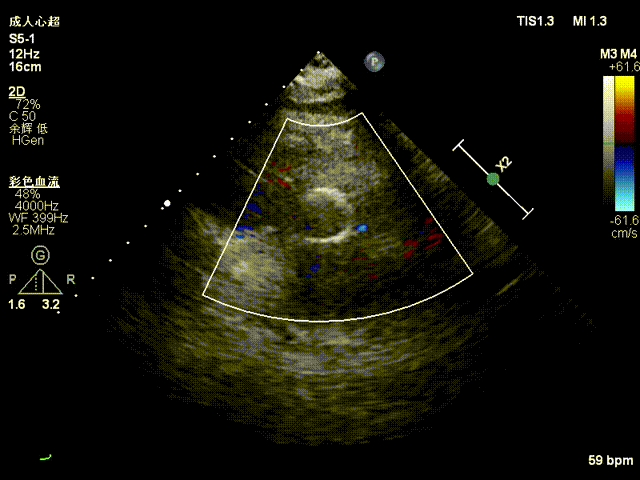

超声影像

血流动力学改善,瓣膜形态良好,无瓣周漏。